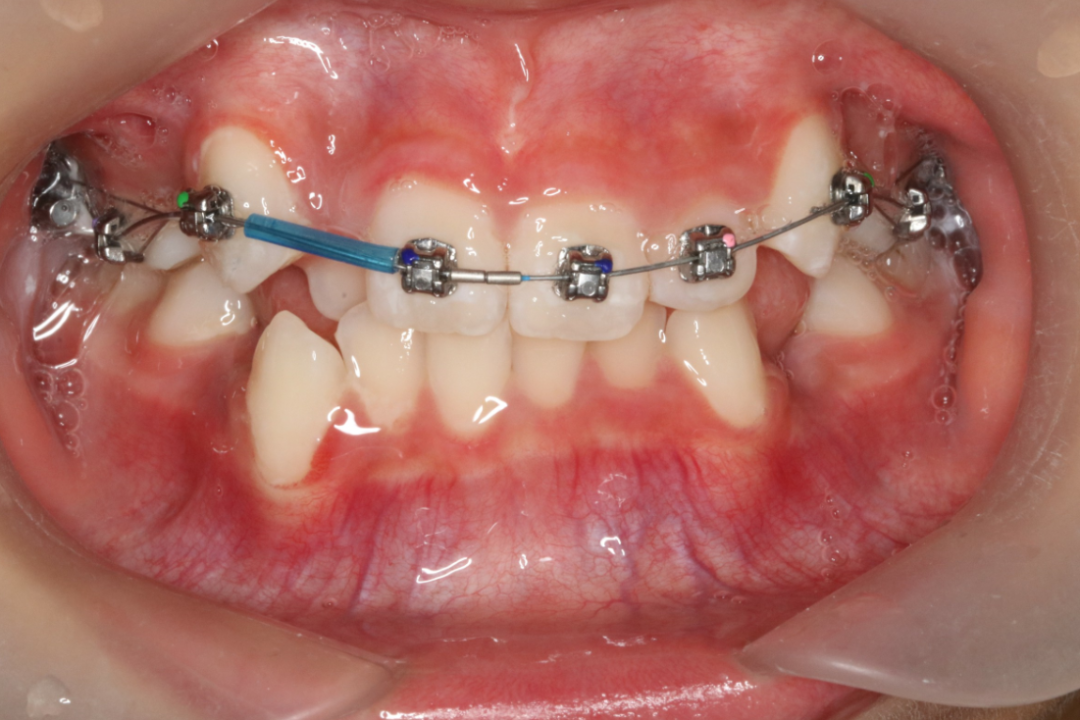

3、一般矫治。根据不同牙颌面畸形选用各类矫治器,一般矫治是口腔正畸矫治中最多见的。如可摘矫治器、功能矫治器、固定矫治器等。近年来,无托槽隐形矫治技术因其美观、舒适的优势渐渐得到人们的青睐,随着口腔正畸医疗技术及材料的不断发展,无托槽隐形矫治技术越来越成熟。目前,大部分错颌畸形可通过无托槽隐形矫治技术纠正。

金属自锁托槽矫治技术

治疗前                        治疗后

儿童错合畸形早期矫治是阻断影响儿童颌骨、牙齿正常发育的因素,促进颌面部正常发育,降低II期矫正的难度,减少II期矫正的时间,甚至不需要II期矫正。让孩子早期获得自信,绽放灿烂笑容。

术前→术后